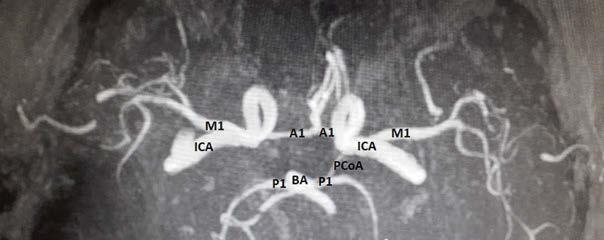

Uzupełnieniem diagnostyki w chorobach naczyniowych mózgowia jest badanie angiograficzne w tomografii komputerowej lub rezonansie magnetycznym, co obecnie stało się standardem postępowania w diagnostyce chorób naczyniowych, zwłaszcza w udarze niedokrwiennym mózgu. W związku z rozwojem interwencyjnego leczenia udaru badania angiograficzne są z powodzeniem wykorzystywane w wizualizacji zwężeń głównych osi naczyniowych zasilających koło tętnicze mózgu oraz okluzji jego części składowych i jego gałęzi jako badanie bezpośrednio poprzedzające trombektomię

mechaniczną w leczeniu ostrej fazy udaru niedokrwiennego mózgu. Do technik, dzięki którym można uzyskać wgląd w układ naczyniowy mózgowia, należy zaliczyć również angiografię klasyczną oraz subtrakcyjną.

Rycina 1.37. Obraz naczyń koła tętniczego mózgu w angiografii rezonansu magnetycznego uzyskane w aparacie o polu elektromagnetycznym 1,5 T. M1 – tętnica środkowa mózgu; A1 – tętnica przednia mózgu; ICA – tętnica szyjna wewnętrzna; P1 – tętnica tylna mózgu; BA – tętnica podstawna; PCoA – tętnica łącząca tylna. Hipoplastyczna PCoA prawa jest niewidoczna na obrazie.